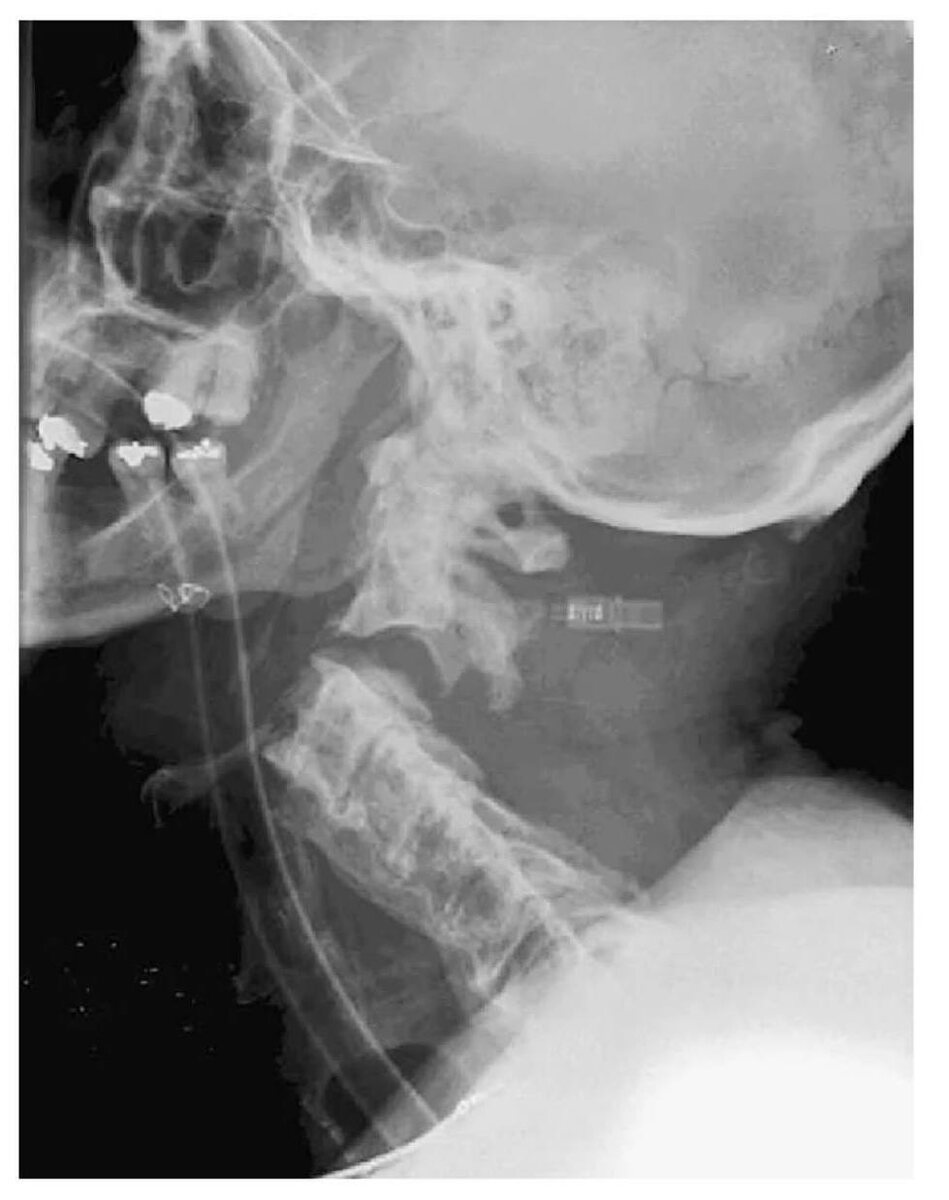

Пациентка 57 лет поступила после ДТП. Несмотря на крайне мерзкий первый снимок, выписалась без существенных неврологических нарушений (картинки из интернета)